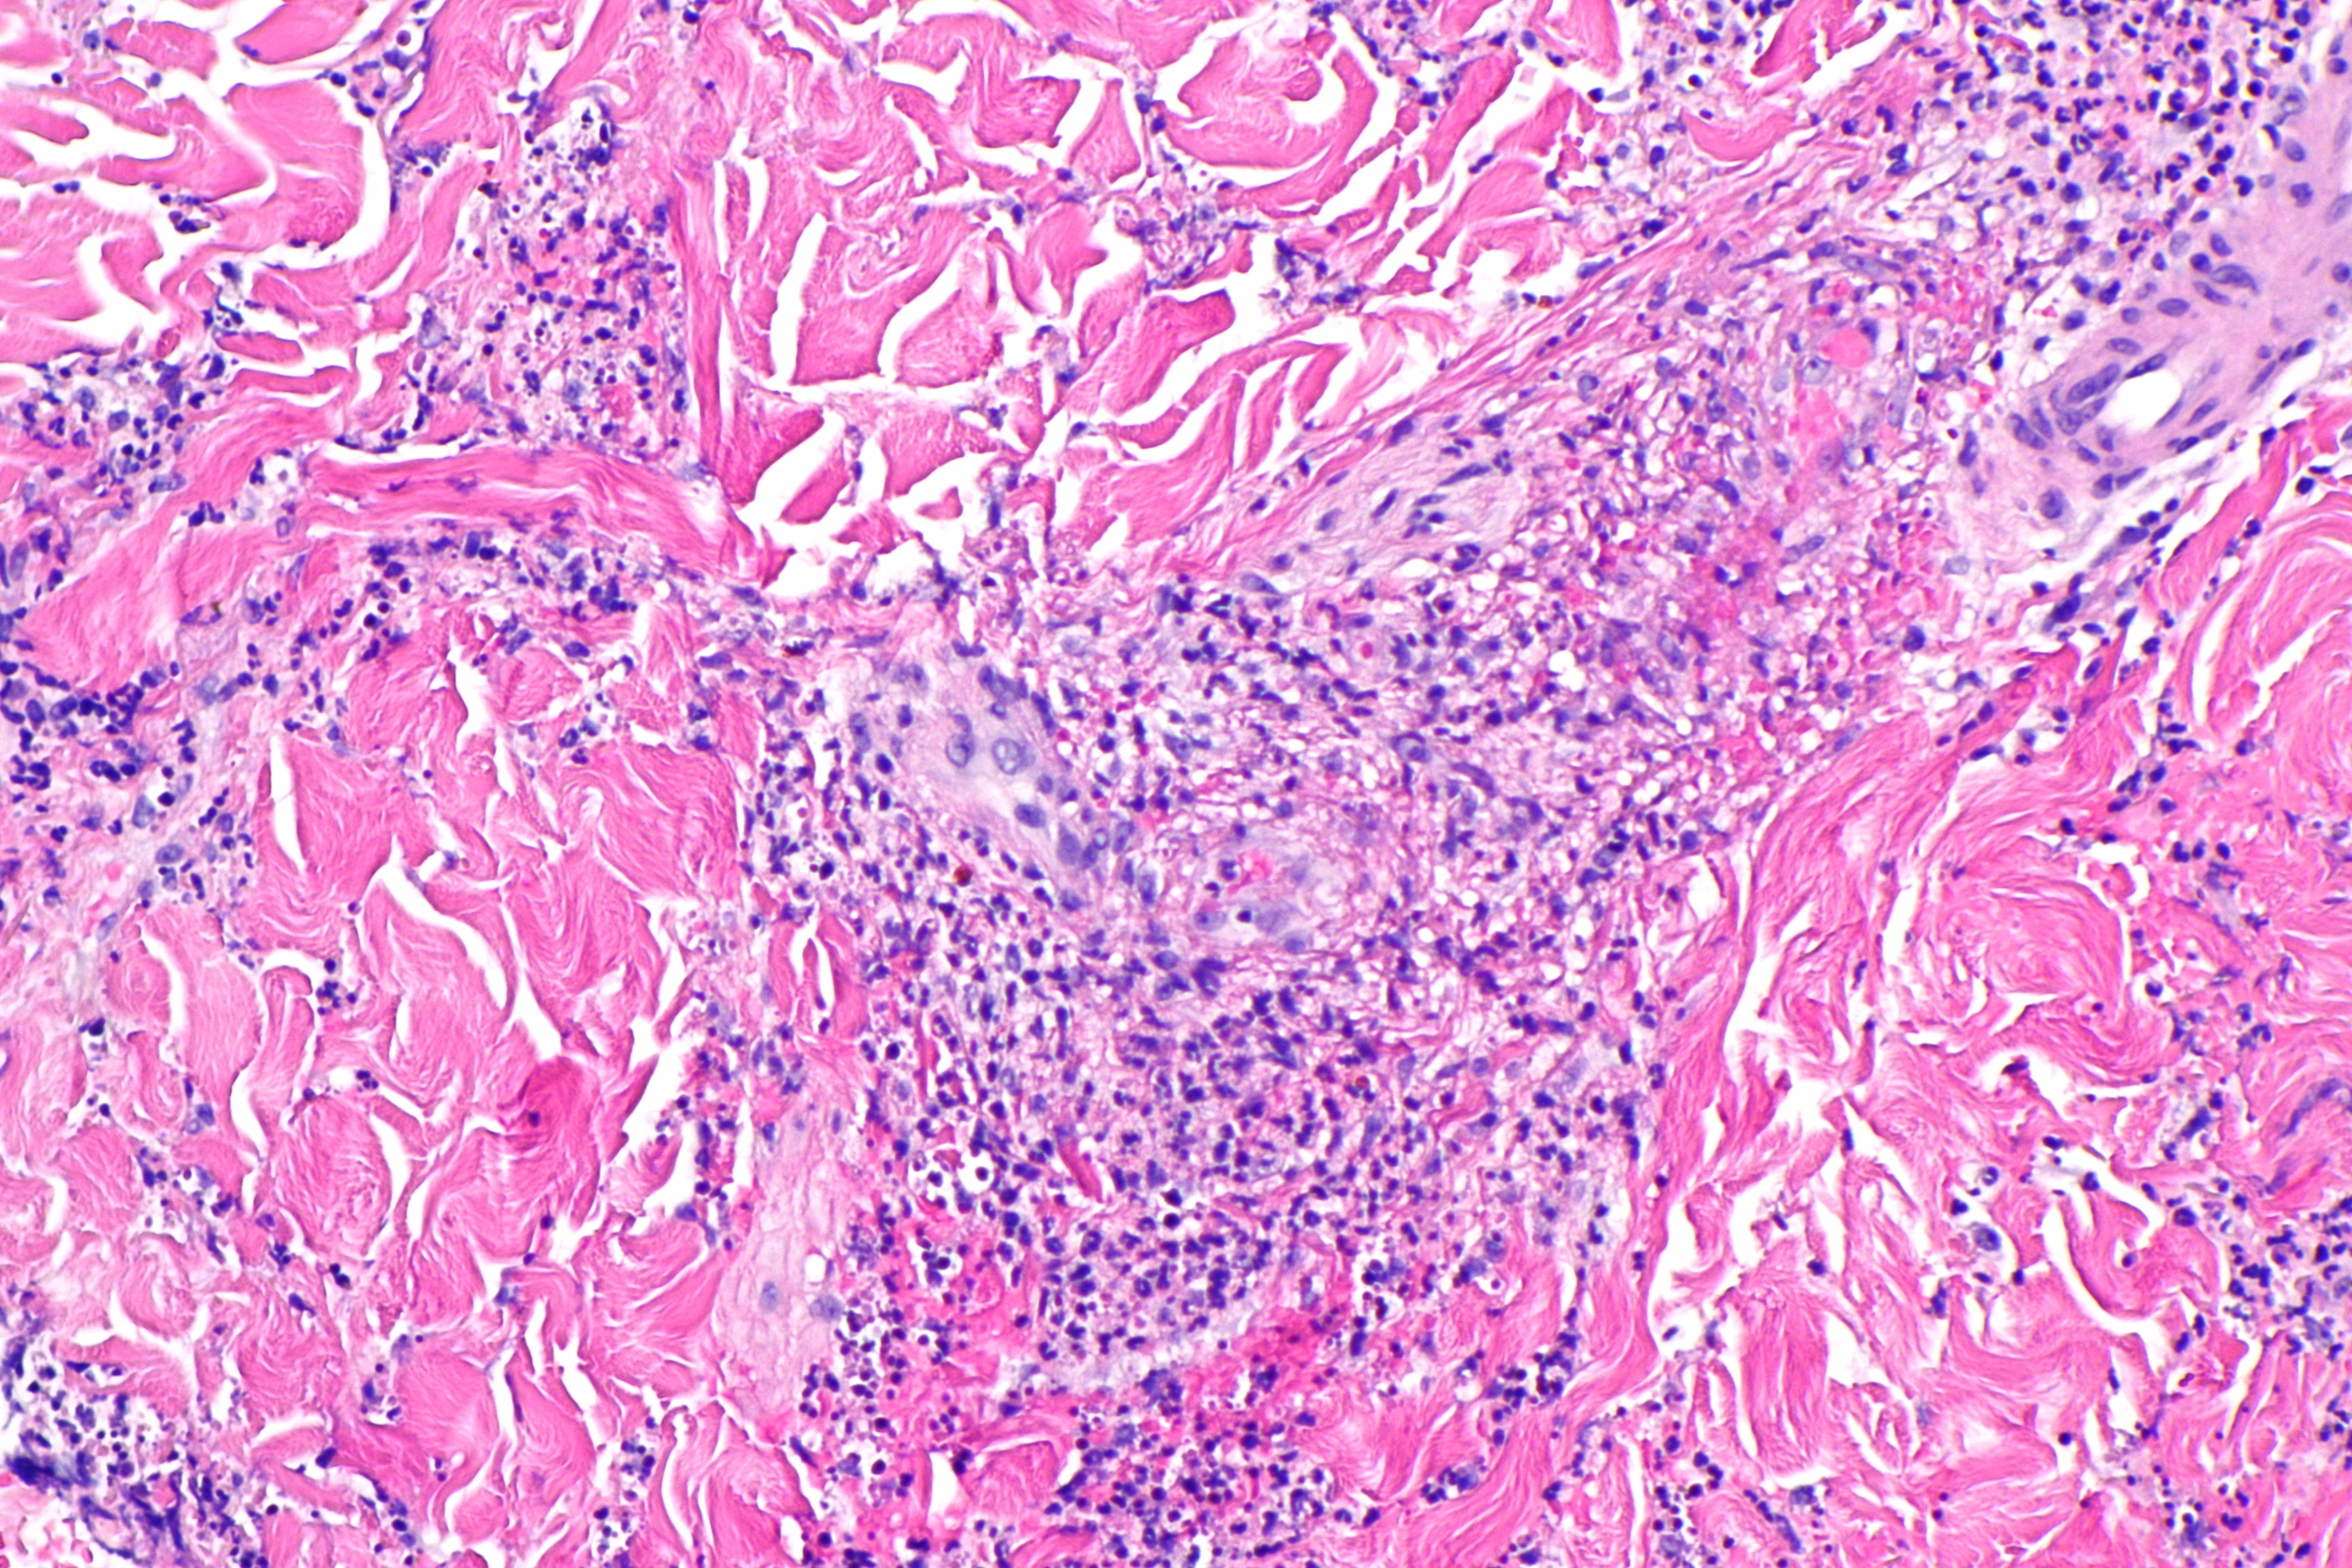

Морфологические изменения при ПВЦНСВыделяют 3 основных гистопатологических варианта ПВЦНС [38, 39]. Наиболее частым из них является гранулематозный васкулит, доля которого среди всех ПВЦНС составляет 58%. Он характеризуется наличием вокруг сосудов мононуклеарного воспаления в сочетании с образованием гранулем в разных слоях сосудистой стенки и наличием полинуклеарных клеток.

Лимфоцитарный васкулит составляет 28% всех случаев ПВЦНС и характеризуется выраженной инфильтрацией сосудистой стенки лимфоцитами, а иногда и плазматическими клетками, что ведет к ее дезорганизации и деструкции. Наличие отдельных периваскулярных мононуклеарных клеток не является основанием для диагностики лимфоцитарного васкулита.

Значительная лимфоцитарная инфильтрация вещества головного мозга при лимфоцитарном васкулите отсутствует [39].

Некротизирующий васкулит встречается в 14% случаев и обычно поражает небольшие артерии мышечного типа. Морфологически изменения напоминают таковые при узелковом полиартериите и характеризуются трансмуральным фибриноидным некрозом с деструкцией внутренней эластической мембраны. Некроз сосудистой стенки является причиной внутримозговых кровоизлияний и микроаневризм. Состояние сосудистой стенки при дифференциальном диагнозе васкулита с другими причинами острых некрозов или кровоизлияний в мозге должно оцениваться вне зон этих повреждений, так как в их пределах изменения сосудистой стенки носят вторичный характер и не являются признаком васкулита [39]. Ишемические изменения в биоптатах головного мозга при ПВЦНС обнаруживаются в 40—51% случаев, чаще всего при некротизирующем васкулите, кровоизлияния — в 12% [39]. Морфологические изменения при ПВЦНС, как правило, обнаруживаются в артериях небольшого и среднего калибра и артериолах, тогда как в венах они выявляются редко [11].

В отдельных случаях находят изолированное поражение вен небольшого и среднего калибра белого вещества полушарий головного мозга и его мягкой мозговой оболочки. В наблюдении J. Mlakar и соавт. оно было представлено гранулематозным воспалением вен в виде аккумуляции эпителиоидных макрофагов с лимфоцитами, расположенными по периферии гранулемы, и отдельными гигантскими клетками типа Лангерганса, рассеянными среди макрофагов и лимфоцитов. Поскольку эндотелий вен практически был интактен, предполагалось, что патогенный антиген, вызвавший воспалительную реакцию вокруг вен, распространялся со стороны их адвентиции [42] и имел сродство к венам.